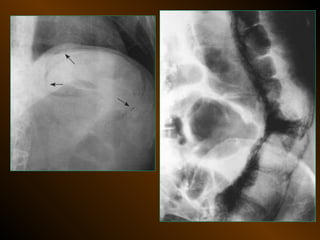

X QUANG CAN THIỆP

KHÍ TỰ DO TRONGKHOANG PHÚC MẠC NGUYÊN NHÂN thủng tạng rỗng nguồn gốc xuyên phúc mạc nguồn gốc trong phúc mạc 10 – 15% thủng tạng rỗng → không thấy hơi tự do ổ bụng